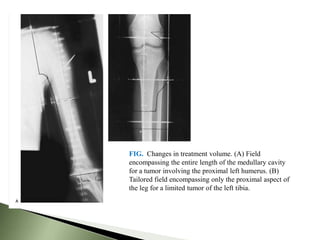

FIG. Changes in treatment volume. (A) Field

encompassing the entire length of the medullary cavity

for a tumor involving the proximal left humerus. (B)

Tailored field encompassing only the proximal aspect of

the leg for a limited tumor of the left tibia.

   Patient may be treated in supine ,prone, or lateral

position site dependent.

   6MV of energy used

   For limb, opposing fields normally used.

   Tailored portals for every patient.

   Field should not cross joints unless essential.

   Entire Medullary cavity need not be included in the

RT portal.

   Try and spare a strip(1-2cm) of normal tissue for

lymph drainage.